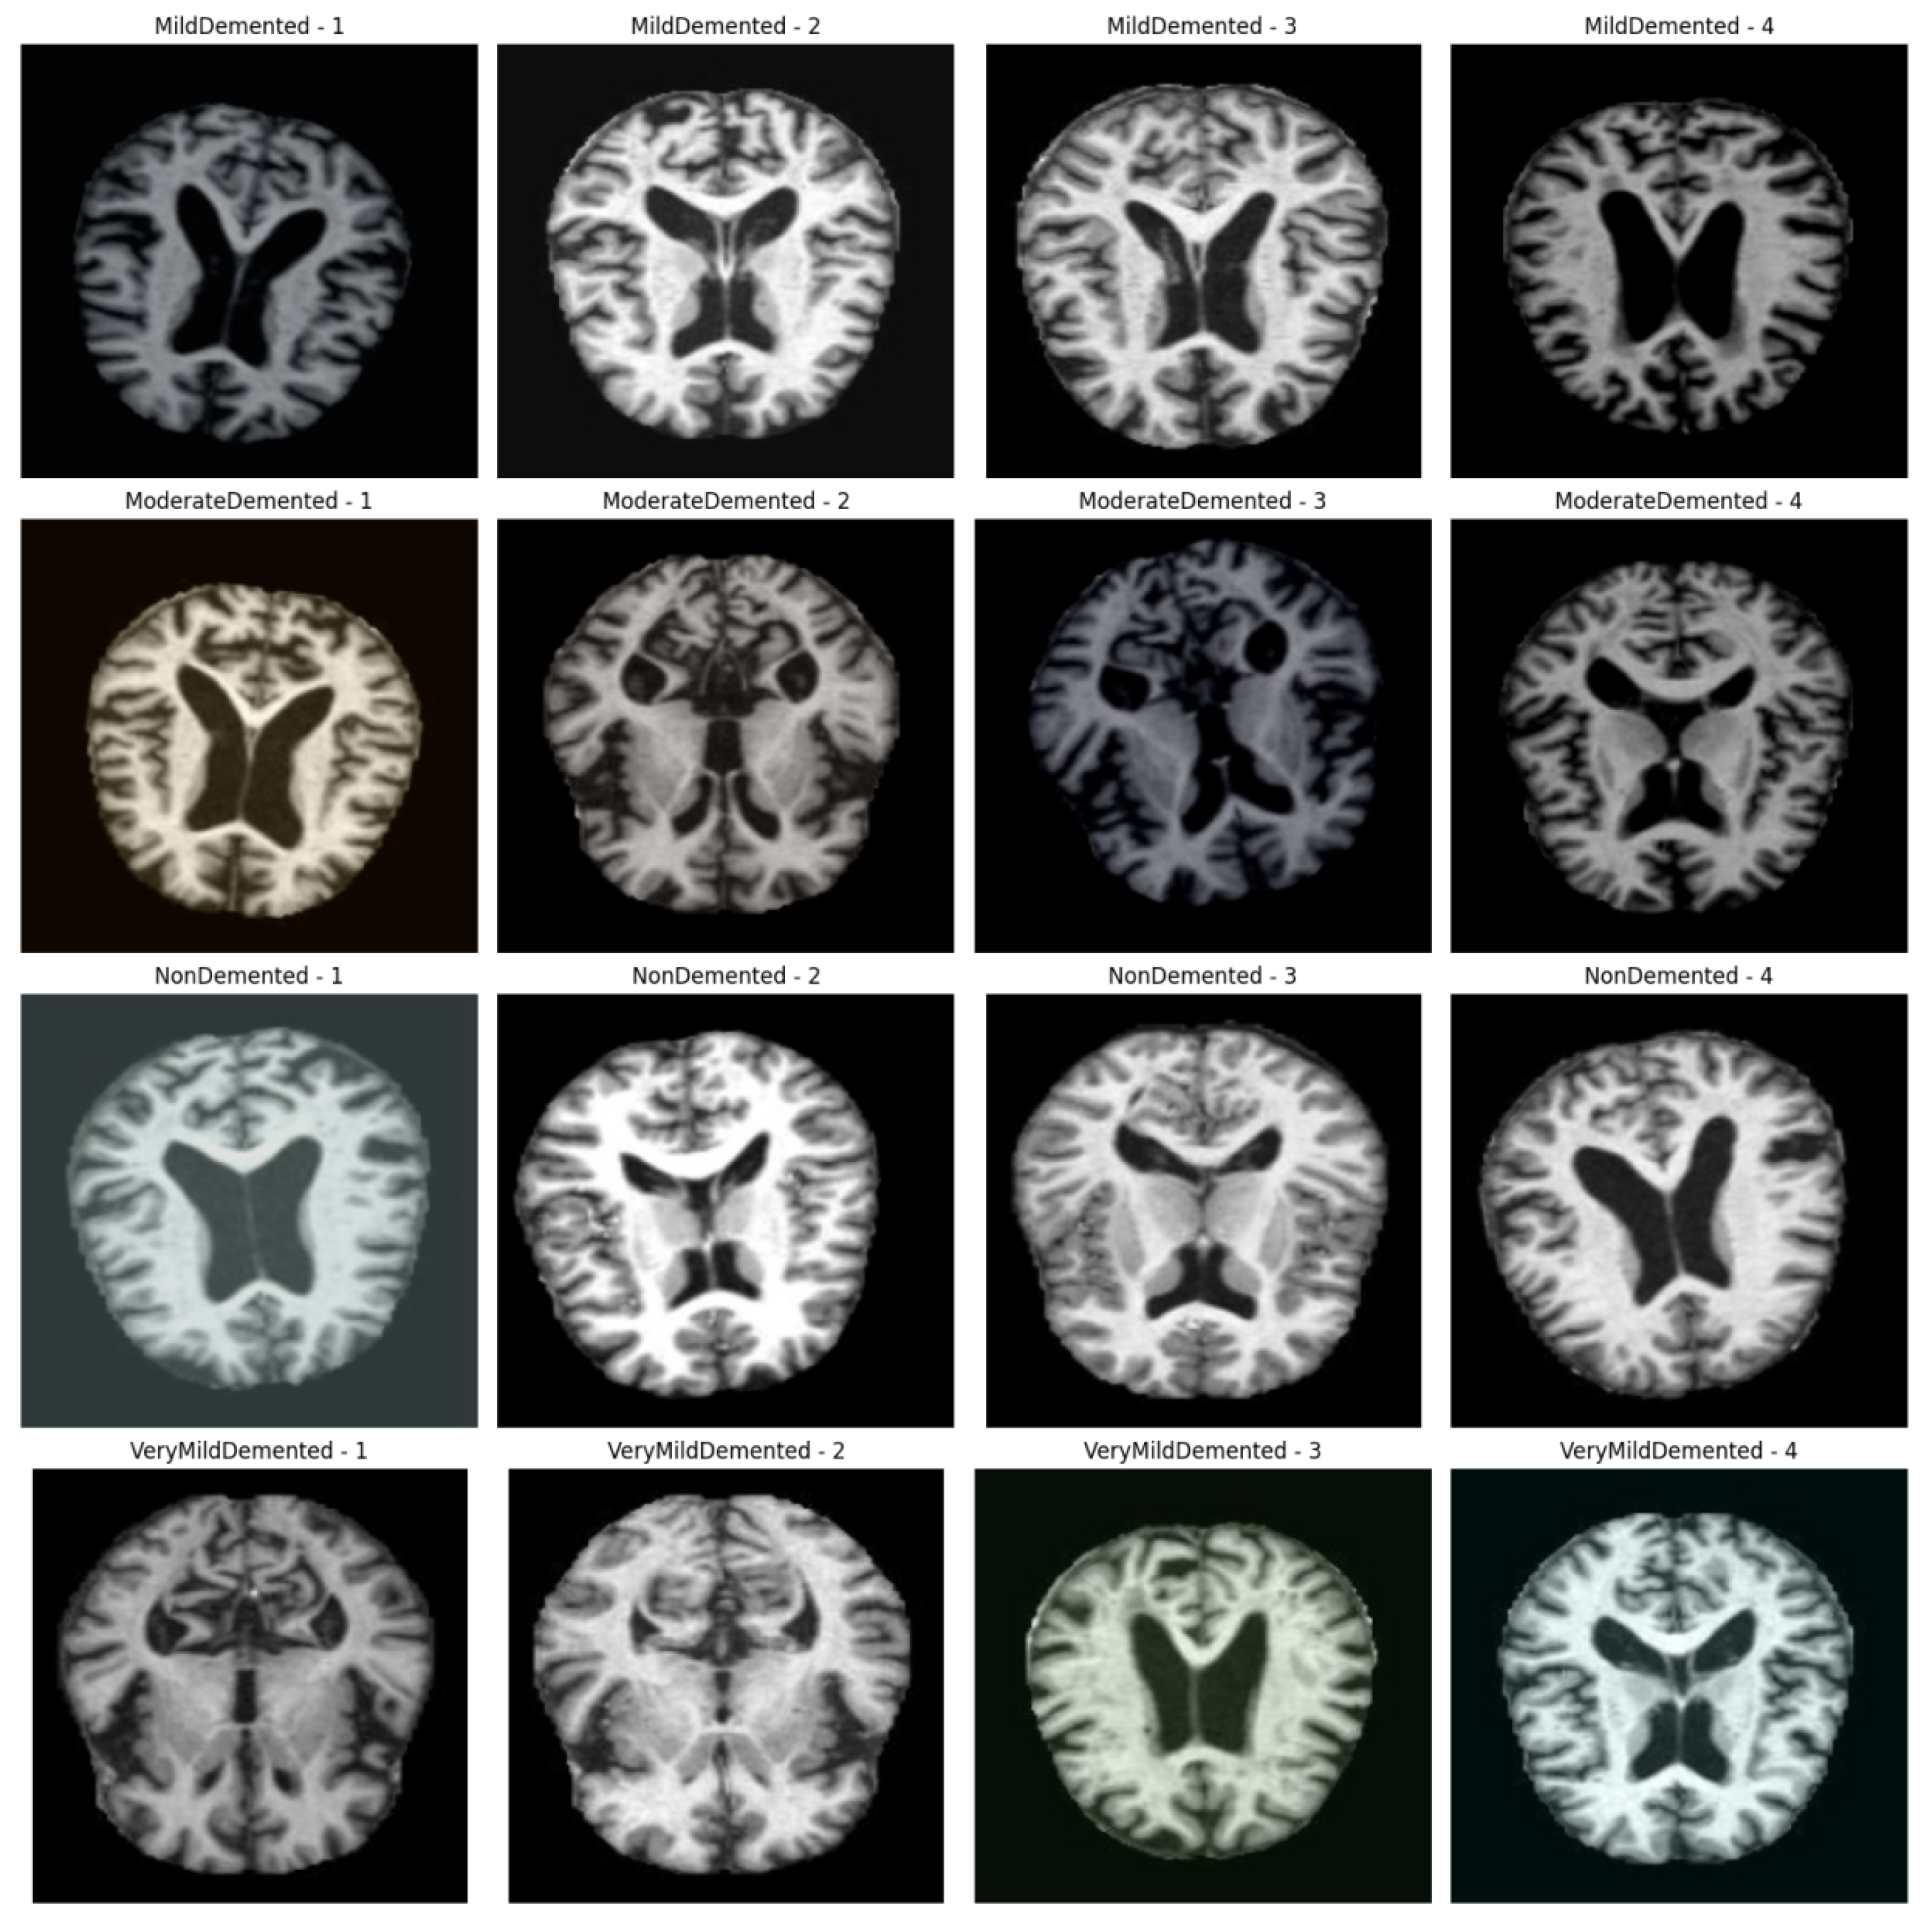

4.1. Data Set

| categories | Number of images after data enhancement |

Number of training sets |

Number of test sets |

|---|---|---|---|

| MildDemented | 8,960 | 7,168 | 1,792 |

| ModerateDemented | 6,464 | 5,171 | 1,293 |

| NonDemented | 9,600 | 7,680 | 1,920 |

| VeryMildDemented | 8,960 | 7,168 | 1,792 |

| total |